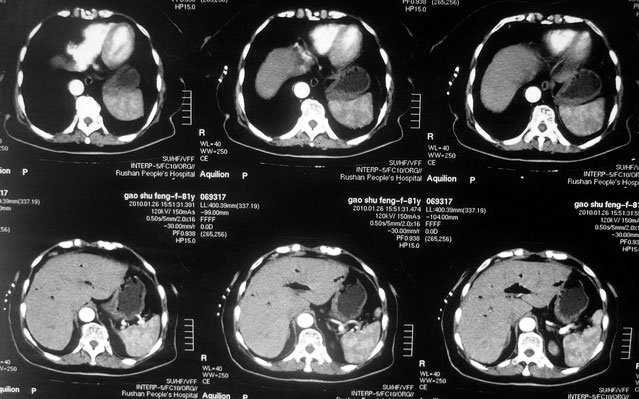

肝癌合并肝脓肿

女,80岁既往有胆系手术史。近2月出现食欲不振,近20天出现畏寒发热,体重约下降10kg,体温一般在38℃左右。血常规wbc正常,中性比例88%,cea 10.3,afp、ca199均正常。做过一次肝穿,抽出约3ml仿佛脓性液体。这是她的增强ct扫描,请大家帮帮忙。另外想问问肝脓肿和胆管细胞癌的ct表现有什么区别。谢谢了。

【湘江一滴】化脓性胆囊炎及胆管炎,肝内胆管积气、积液、扩张;胆囊壁增厚、强化;胆周积液。未见肝内占位征象。

【shuiyuan】化脓性胆囊炎及胆管炎,肝内胆管积气、积液、扩张;胆囊壁增厚、强化;胆周积液.

肝脓肿动脉期呈明显环形强化或蜂窝状强化,胆管细胞癌动脉期强化不明显,且伴肝内胆管扩张。

【zenxisengming 】肝内胆管扩张积气,胆囊比环形增厚,胆囊周围渗出,未见占位性病变,应该是胆道化脓性感染

【sunbin】肝内见多个气体密度影伴气液面,胆囊壁增厚,胆囊周围低密度环绕,未见强化,支持化脓性胆管炎、胆囊炎。

最近复查ct,做了第二次穿刺抽脓,顺便做了涂片病理活检,结果找到恶性肿瘤细胞,诊断肝癌合并肝脓肿。看来大家都走眼了啊。